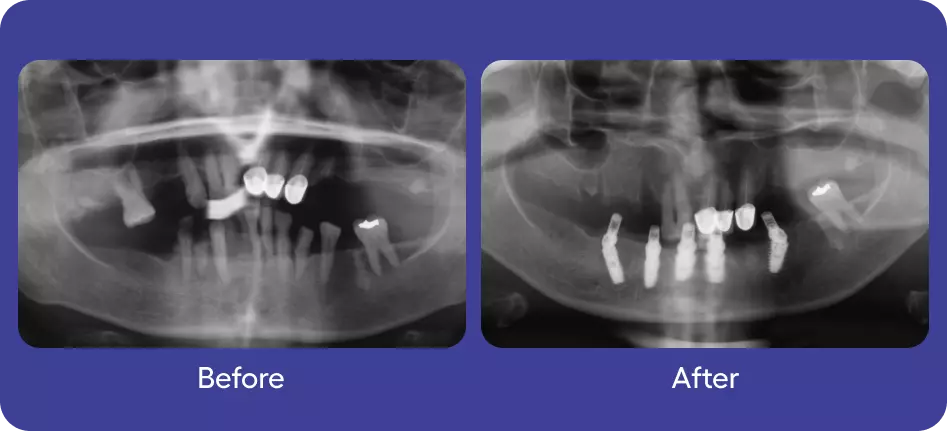

Implants

Full Mouth Rehabilitation